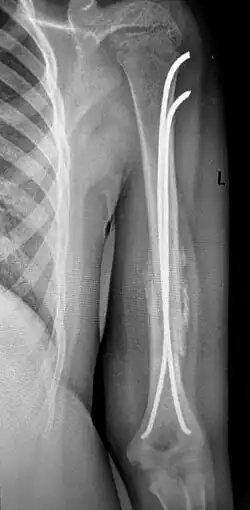

Рентгенограмма при диафизарном переломе плеча. Переломы плеча в среднем отделе (диафизарные переломы плеча) возникают в результате падения на руку или удара по плечу, могут быть косыми, поперечными, винтообразными и оскольчатыми. Диафизарные переломы плеча нередко сочетаются с повреждением лучевого нерва. Возможно повреждение плечевых артерий и вен.

Клиническими признаками перелома плеча являются боли, отёчность, деформация, крепитация костных фрагментов и патологическая подвижность плечевой кости. При переломах плеча с повреждением лучевого нерва пациент не может самостоятельно разогнуть пальцы и кисть. Для уточнения диагноза и выбора тактики лечения выполняют рентгенографическое исследование.

Переломы плеча без смещения фиксируют гипсовой лангетой, с последующей её заменой на закрытую повязку типа «Дезо» или «Вильпо». При этом контролируется сопоставление отломков с помощью рентгенограмм в разных проекциях. Общий срок иммобилизации при консервативном лечении диафизарных переломов плечевой кости составляет 3-3,5 месяца.

Консервативное лечение целесообразно только в редких случаях: при переломах без смещения или при минимальном смещении отломков, а также при возникновении противопоказаний к операции. В остальных случаях показано оперативное лечение, так как современные малоинвазивные и другие методы фиксации позволяют уже через 3-4 недели начинать разработку движений в плечевом и локтевом суставах, что в свою очередь, предупреждает возникновение тяжёлых контрактур в этих суставах. При повреждении лучевого нерва вследствие перелома проводят оперативное лечение с обязательной ревизией нерва, с адекватной фиксацией отломков.

Хирургическое лечение также показано при многооскольчатых переломах плеча, невозможности закрытой репозиции, интерпозиции мягких тканей и повреждении сосудов и нервов. Фиксацию отломков осуществляют при помощи пластин, интрамедуллярных штифтов с блокированием, или аппарата Илизарова.